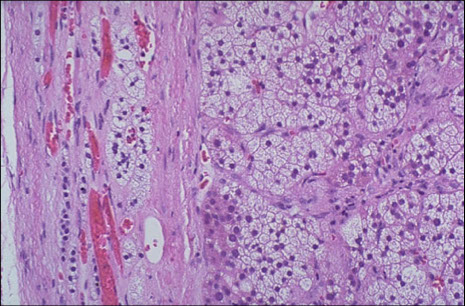

Adrenal Cortical Adenoma

Microscopically, the adrenal cortical adenoma at the right resembles normal adrenal fasciculata. The capsule of this benign neoplasm is at the left. There may be minimal cellular pleomorphism within adenomas